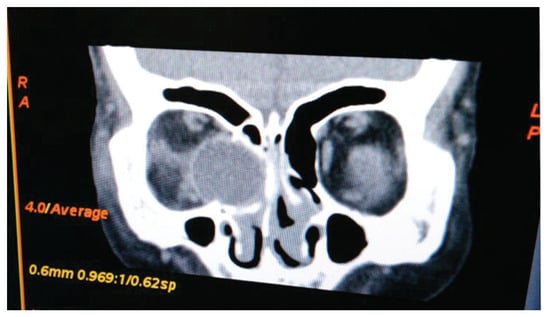

Diagnostic Assessment